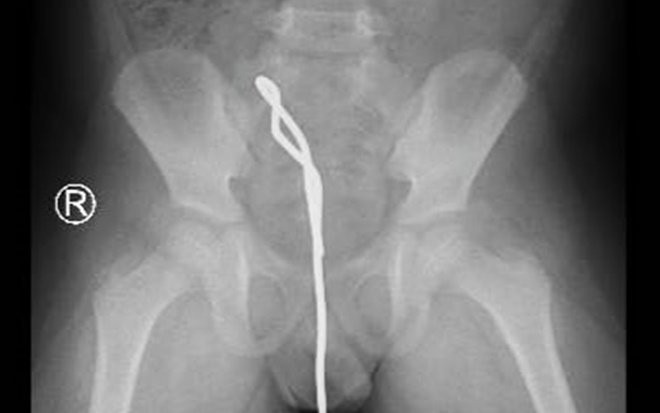

Ngày 5/1, Bệnh viện Nhi đồng Thành phố (TP.HCM) cho biết, bệnh viện vừa tiếp nhận cấp cứu bé trai 6 tuổi (ngụ huyện Cần Giộc, Long An) vì nhét thanh sắt thông cống dài hơn nửa mét vào hậu môn và dính luôn trong bụng.

Tại bệnh viện, bác sĩ Nguyễn Thị Cẩm Xuyên và ekip mổ cấp cứu khẩn trương nội soi ổ bụng thám sát và thấy đoạn ruột sigma bị bầm máu, chưa thấy thủng ruột.

Các bác sĩ kiểm tra hậu môn thì thấy cạnh sắt ghim chặt vào thành sau trực tràng. Kết hợp nội soi ngả bụng và hậu môn, các bác sĩ đã lấy thanh sắt ra ngoài theo ngả hậu môn.